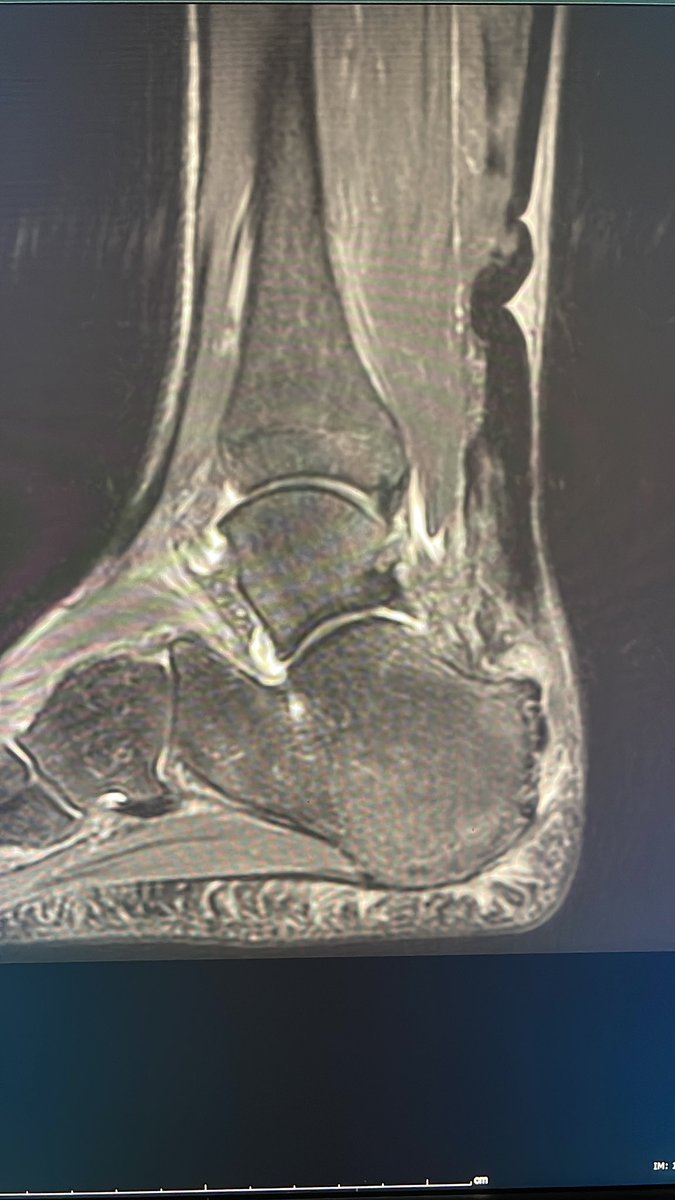

Achilles’ tendon rupture in soccer player. MR in 2020 versus 2022 shows progression to full thickness tear of distal Achilles’ tendon. The distal 2.5 inches is most prone to rupture especially in the setting of chronic trauma due to less blood flow which may also impair healing.